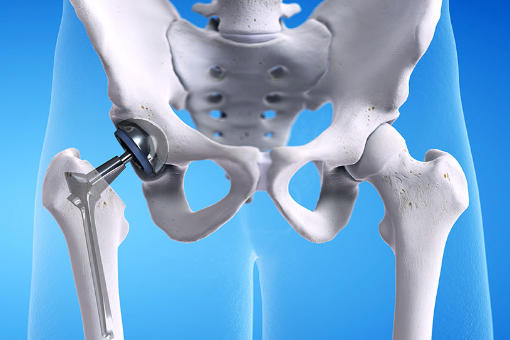

고관절 치환술(Total Hip Arthroplasty)

적응증: 고관절 치환술은 고관절 골관절염, 류마티스 관절염, 무혈성 괴사 또는 고관절 골절이 있는 개인에게 일반적으로 수행됩니다.

절차: 고관절 치환술 중 손상된 고관절의 볼-소켓 구성 요소를 인공 부품으로 교체합니다. 이 절차는 다양한 수술적 접근법을 사용하여 수행될 수 있습니다.

혜택: 고관절 치환술은 통증을 완화하고 고관절 기능을 회복하며 환자가 독립성과 이동성을 회복할 수 있도록 해줍니다.